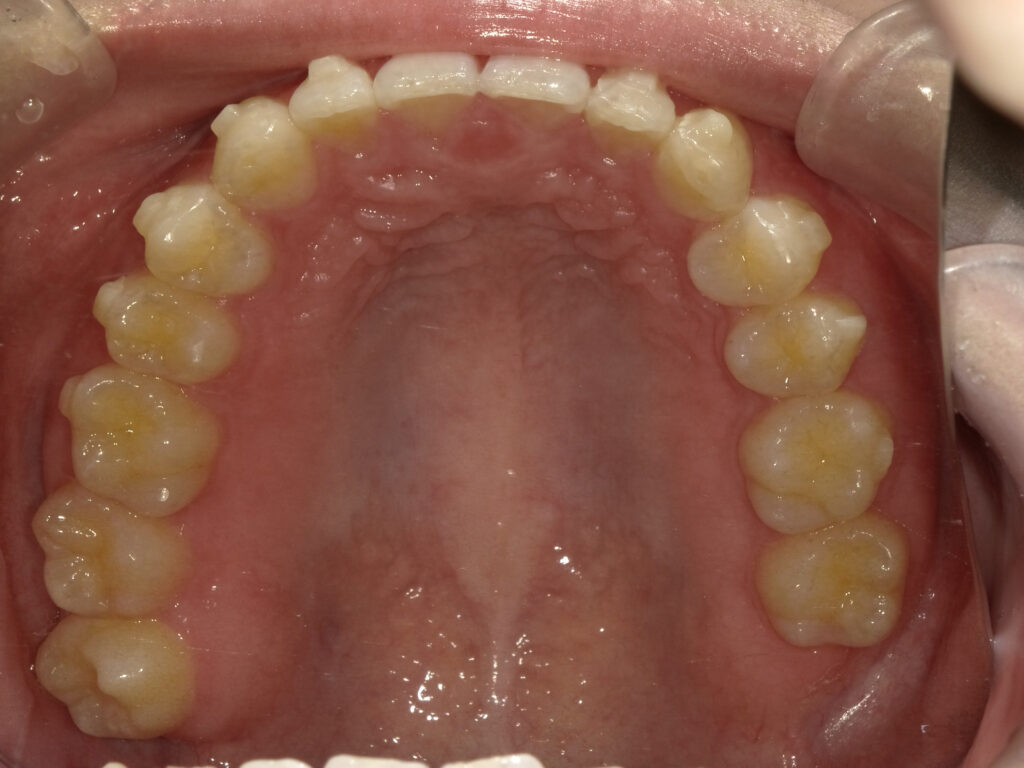

上顎

治療後